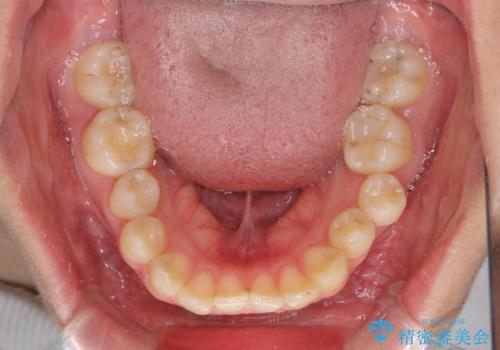

上下の抜歯位置を変えることで、左右ともに理想的な咬み合わせを達成することができました。

横顔の印象はほとんど変わらないものの、唇を閉じたときに前に出ていた下唇が、治療後には少し下がった状態に仕上げることができました。